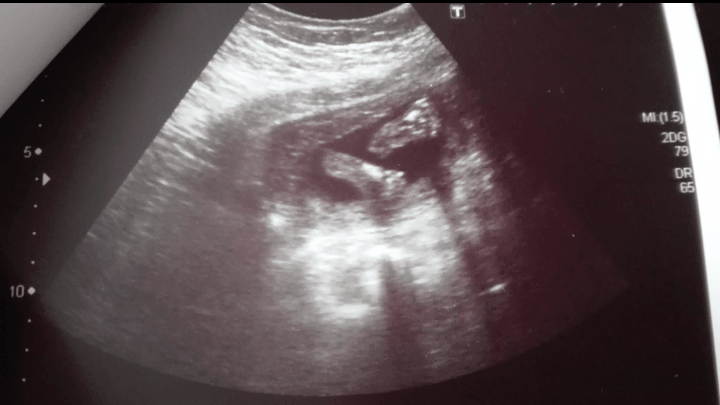

Słodkie! [emoji7] ja mam na zdjęciu jedna stopkę :) zaczęłam wczoraj 23 tydzień i widać już i czuć kopniaki mojego małego na zewnątrz! :) ostatnio spać mi po nocach nie daje, uciska mi pęcherz, przyciąga się.. A jak u Was dziewczyny?:)